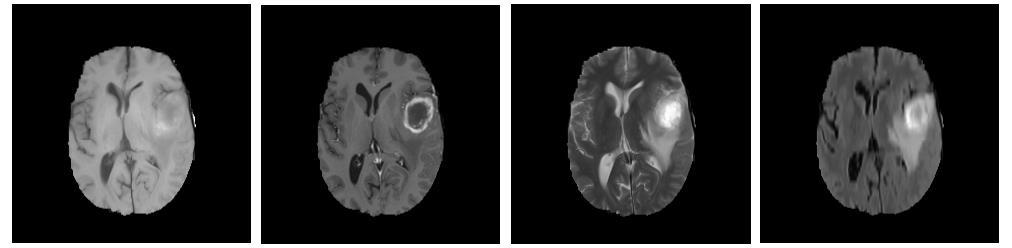

Refer to caption

Figure 1: Four different MRI modalities showing a high grade glioma, each enhancing different subregions of the tumor. From left; T1, T1-Gd, T2, and FLAIR [2]

Tumors may start in the brain, or cancer elsewhere in the body may spread to the brain. Four standard MRI modalities used in brain image study are T1-weighted MRI (T1), T2-weighted MRI (T2), T1-weighted MRI with gadolinium contrast enhancement (T1-Gd), and Fluid Attenuated Inversion Recovery (FLAIR).Generally, T1 images are used for distinguishing healthy tissues, and in this project, we use T1 brain images for our study.